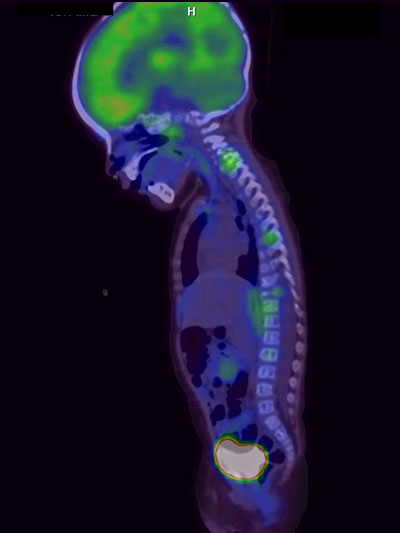

PET/ct (tomografía por emisión de positrones)

- PET/ct

- Oncología (cáncer)

- Neurociencias (enfermedades del cerebro)

- Infecciones

- Hematología (enfermedades de la sangre)

- Tomografía por emisión de positrones (PET/ct)

- 18F-FluoroDesoxiGlucosa (18F-FDG)

¿POR QUÉ MI MÉDICO NECESITA UN ESTUDIO DE MEDICINA NUCLEAR E IMAGEN MOLECULAR (PET/ct; SPECT/ct Gammagrafía?

Porque la información que aportan estos estudios es muy valiosa para tener un diagnóstico preciso, un diagnóstico más temprano o ambas.